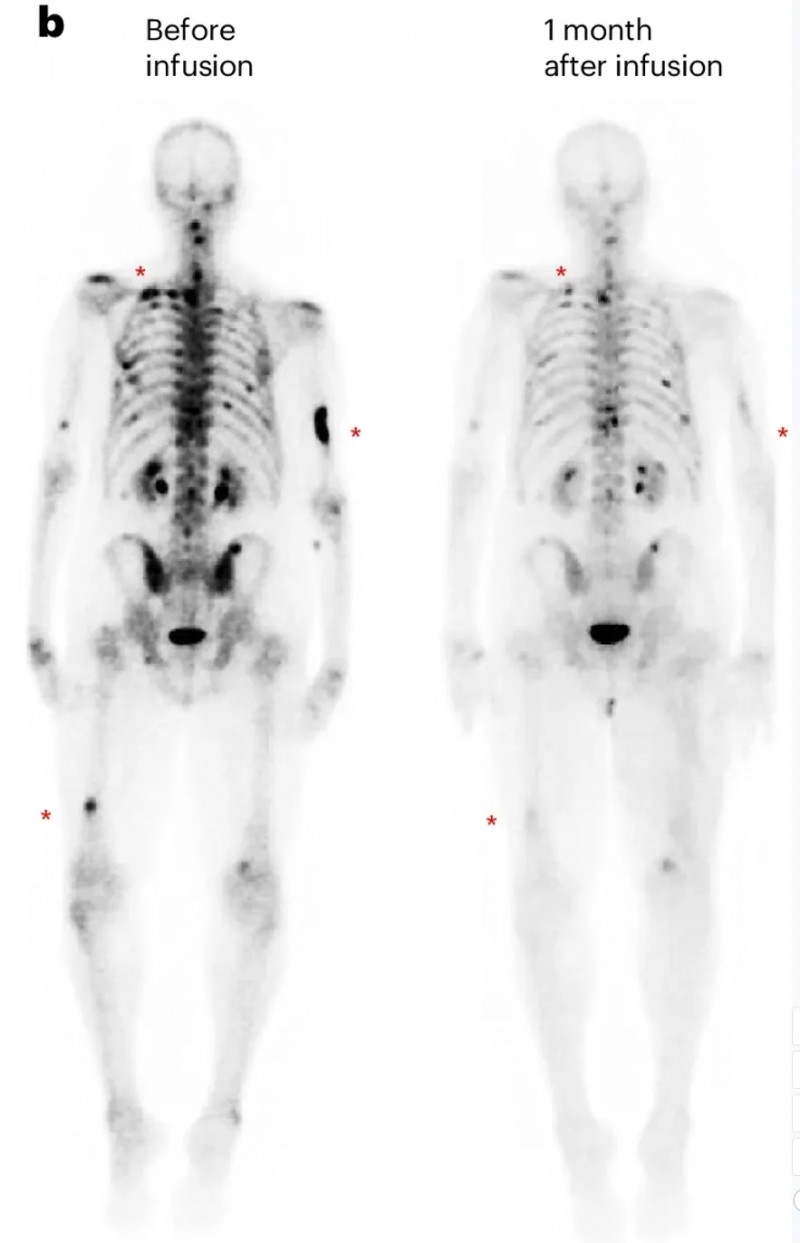

第一例为DL3剂量组患者(UPN394),其肝转移负荷实现放射学改善,但未达到PSA反应;CT扫描清晰呈现了输注前的肝转移灶,以及输注PSCA-CAR-T细胞1个月后的疾病反应(详见下图c)。

▲图源“Nature Medicine”,版权归原作者所有,如无意中侵犯了知识产权,请联系我们删除